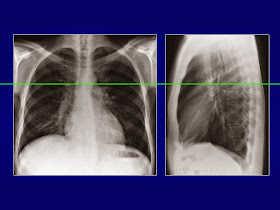

Chụp cắt lớp vi tính (CLVT) phổi và lồng ngực đánh giá được tình trạng bệnh lý của xương sườn, màng phổi, nhu mô phổi, phế quản, tim, mạch máu, trung thất…. Dựa vào hình ảnh chụp CLVT có thể nhìn thấy những bất thường mà không thể phát hiện dễ trên phim chụp X quang tiêu chuẩn thẳng hoặc nghiêng vì bị các tạng khác chồng lên che khuất.CT scanner là một phần của cắt lớp vi tính trong chẩn đoán hình ảnh. Để học được CT lồng ngực thì chúng ta cũng phải có những bước cơ bản trước. Đó là phải cần học giải phẫu trước. CT có độ phân giải cao hơn so với X quang thường quy, có độ chi tiết hơn vì vậy sẽ có nhiều chi tiết hơn. Đối với người bắt đầu học CT thì việc học giải phẫu sẽ khó khăn hơn chút. Để giúp ích cho việc học sau này tôi xin giới thiệu loạt slide bài giảng về giải phẫu lồng ngực. Bài giảng chỉ các mốc giải phẫu cơ bản lồng ngực qua các lát cắt. Hình ảnh minh họa dễ hiểu. Các bạn có thể bấm vào ảnh để xem ảnh phóng to để nhìn rõ các mốc giải phẫu như phân thùy phổi(thùy phải: 3 thùy; thùy trái:2 thùy), trung thất, xương.

| Click vào ảnh để phóng to |